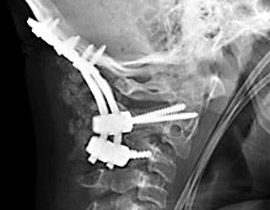

قام الاطباء بتثبيت رقبته إلى جسده بالمسامير |

وعقب حصول الحادث في أواخر العام 2006، قام الأطباء بإخضاع الصبي المصاب إلى عملية جراحية عاجلة استمرت لمدة 7 ساعات، وهي العملية التي نجحوا خلالها في إعادة تثبيت فقرات رقبته وتوصيلها إلى قاعدة الجمجمة باستخدام مسامير وشرائح مصنوعة من معدن التيتانيوم.